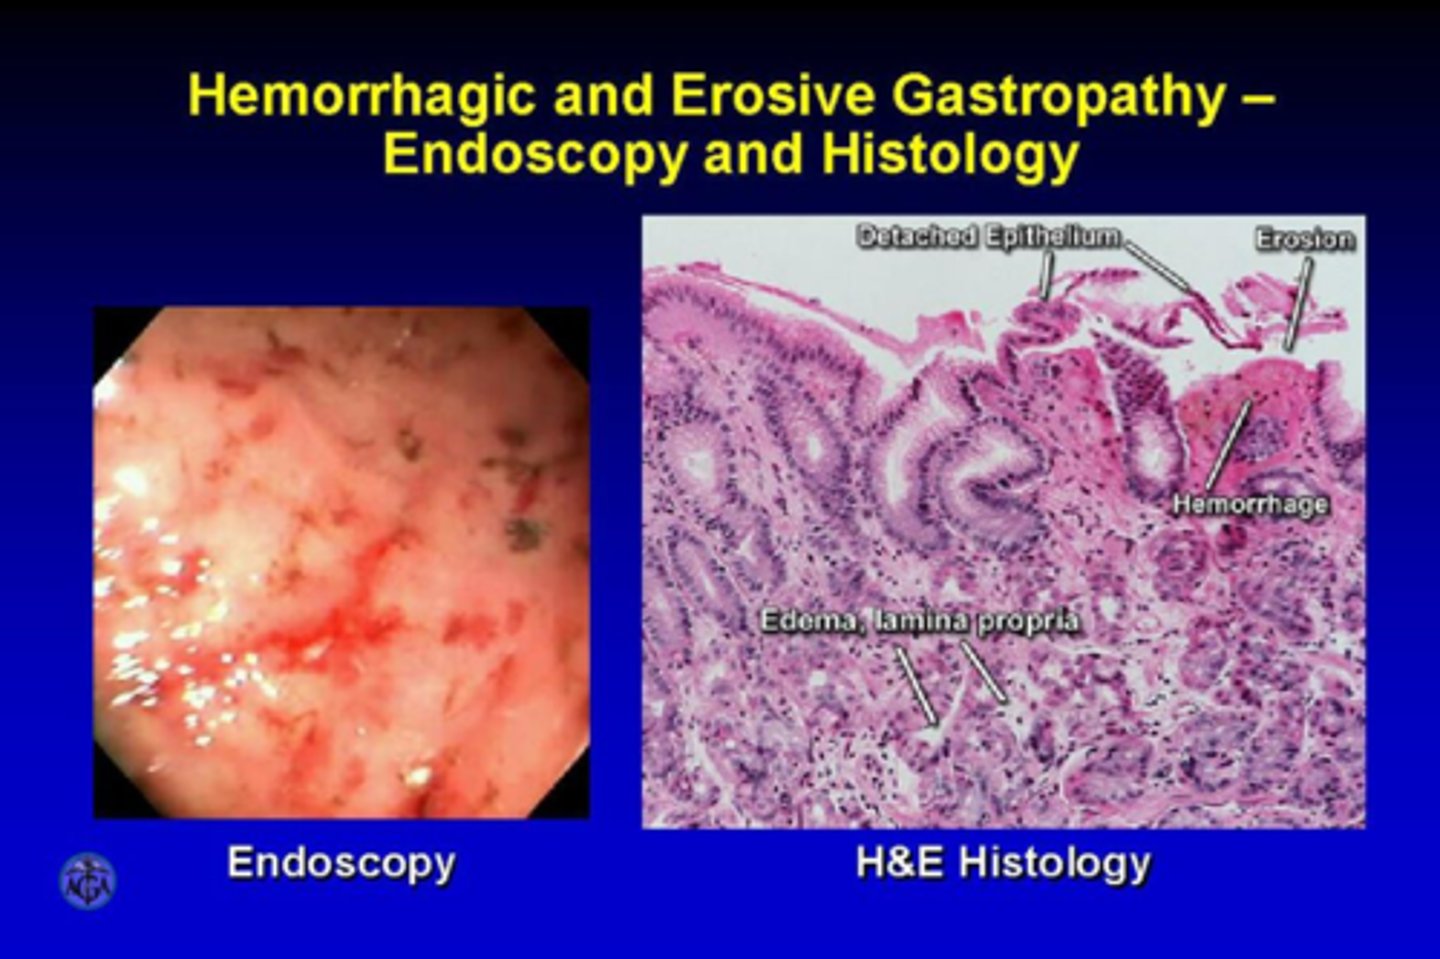

What is the most common cause of gastropathy?

NSAIDs

Alcohol

Portal Hypertension

Medical/surgical stress

What are the signs and symptoms of Gastropathy?

Asymptomatic usually but may present with upper GI bleeding with hematemesis or melena

What is the most common clinical manifestation of erosive gastropathy?

Melena

What is the most common clinical manifestation of erosive gastropathy?

Melena

Linda is an alcoholic and she also currently started taking ibuprofen for her neck pain. She comes into the ER with N/V and epigastric pain. Her BMI is below normal. She states she has vomited blood multiple times within the past week. She describes it to have a "coffee ground" appearance.

What tests do you order?

Endoscopy to see if Linda has errosive or hemorrhagic gastropathy.

You can also order a CBC and hemoccult.